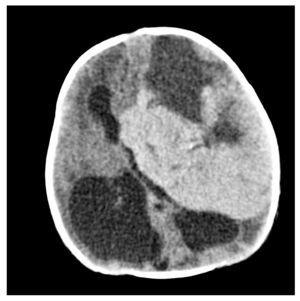

Fig. 3.